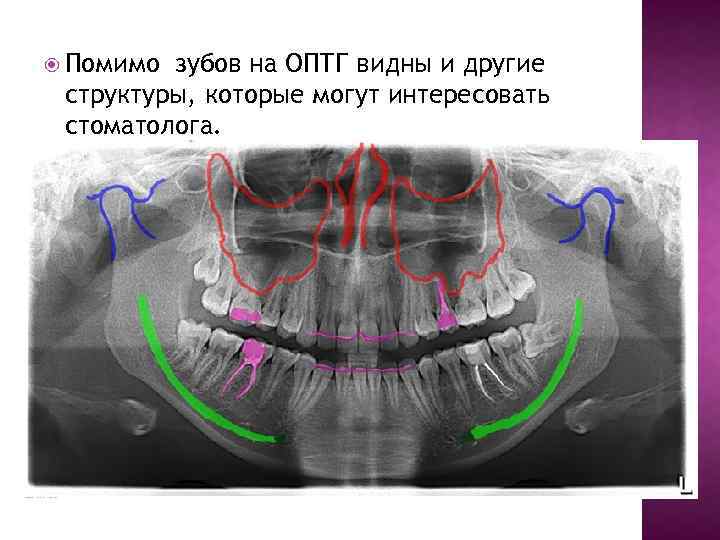

Помимо зубов на ОПТГ видны и другие структуры, которые могут интересовать стоматолога.

Также на ОПТГ есть структуры, которые не очень интересуют, но все же видны.